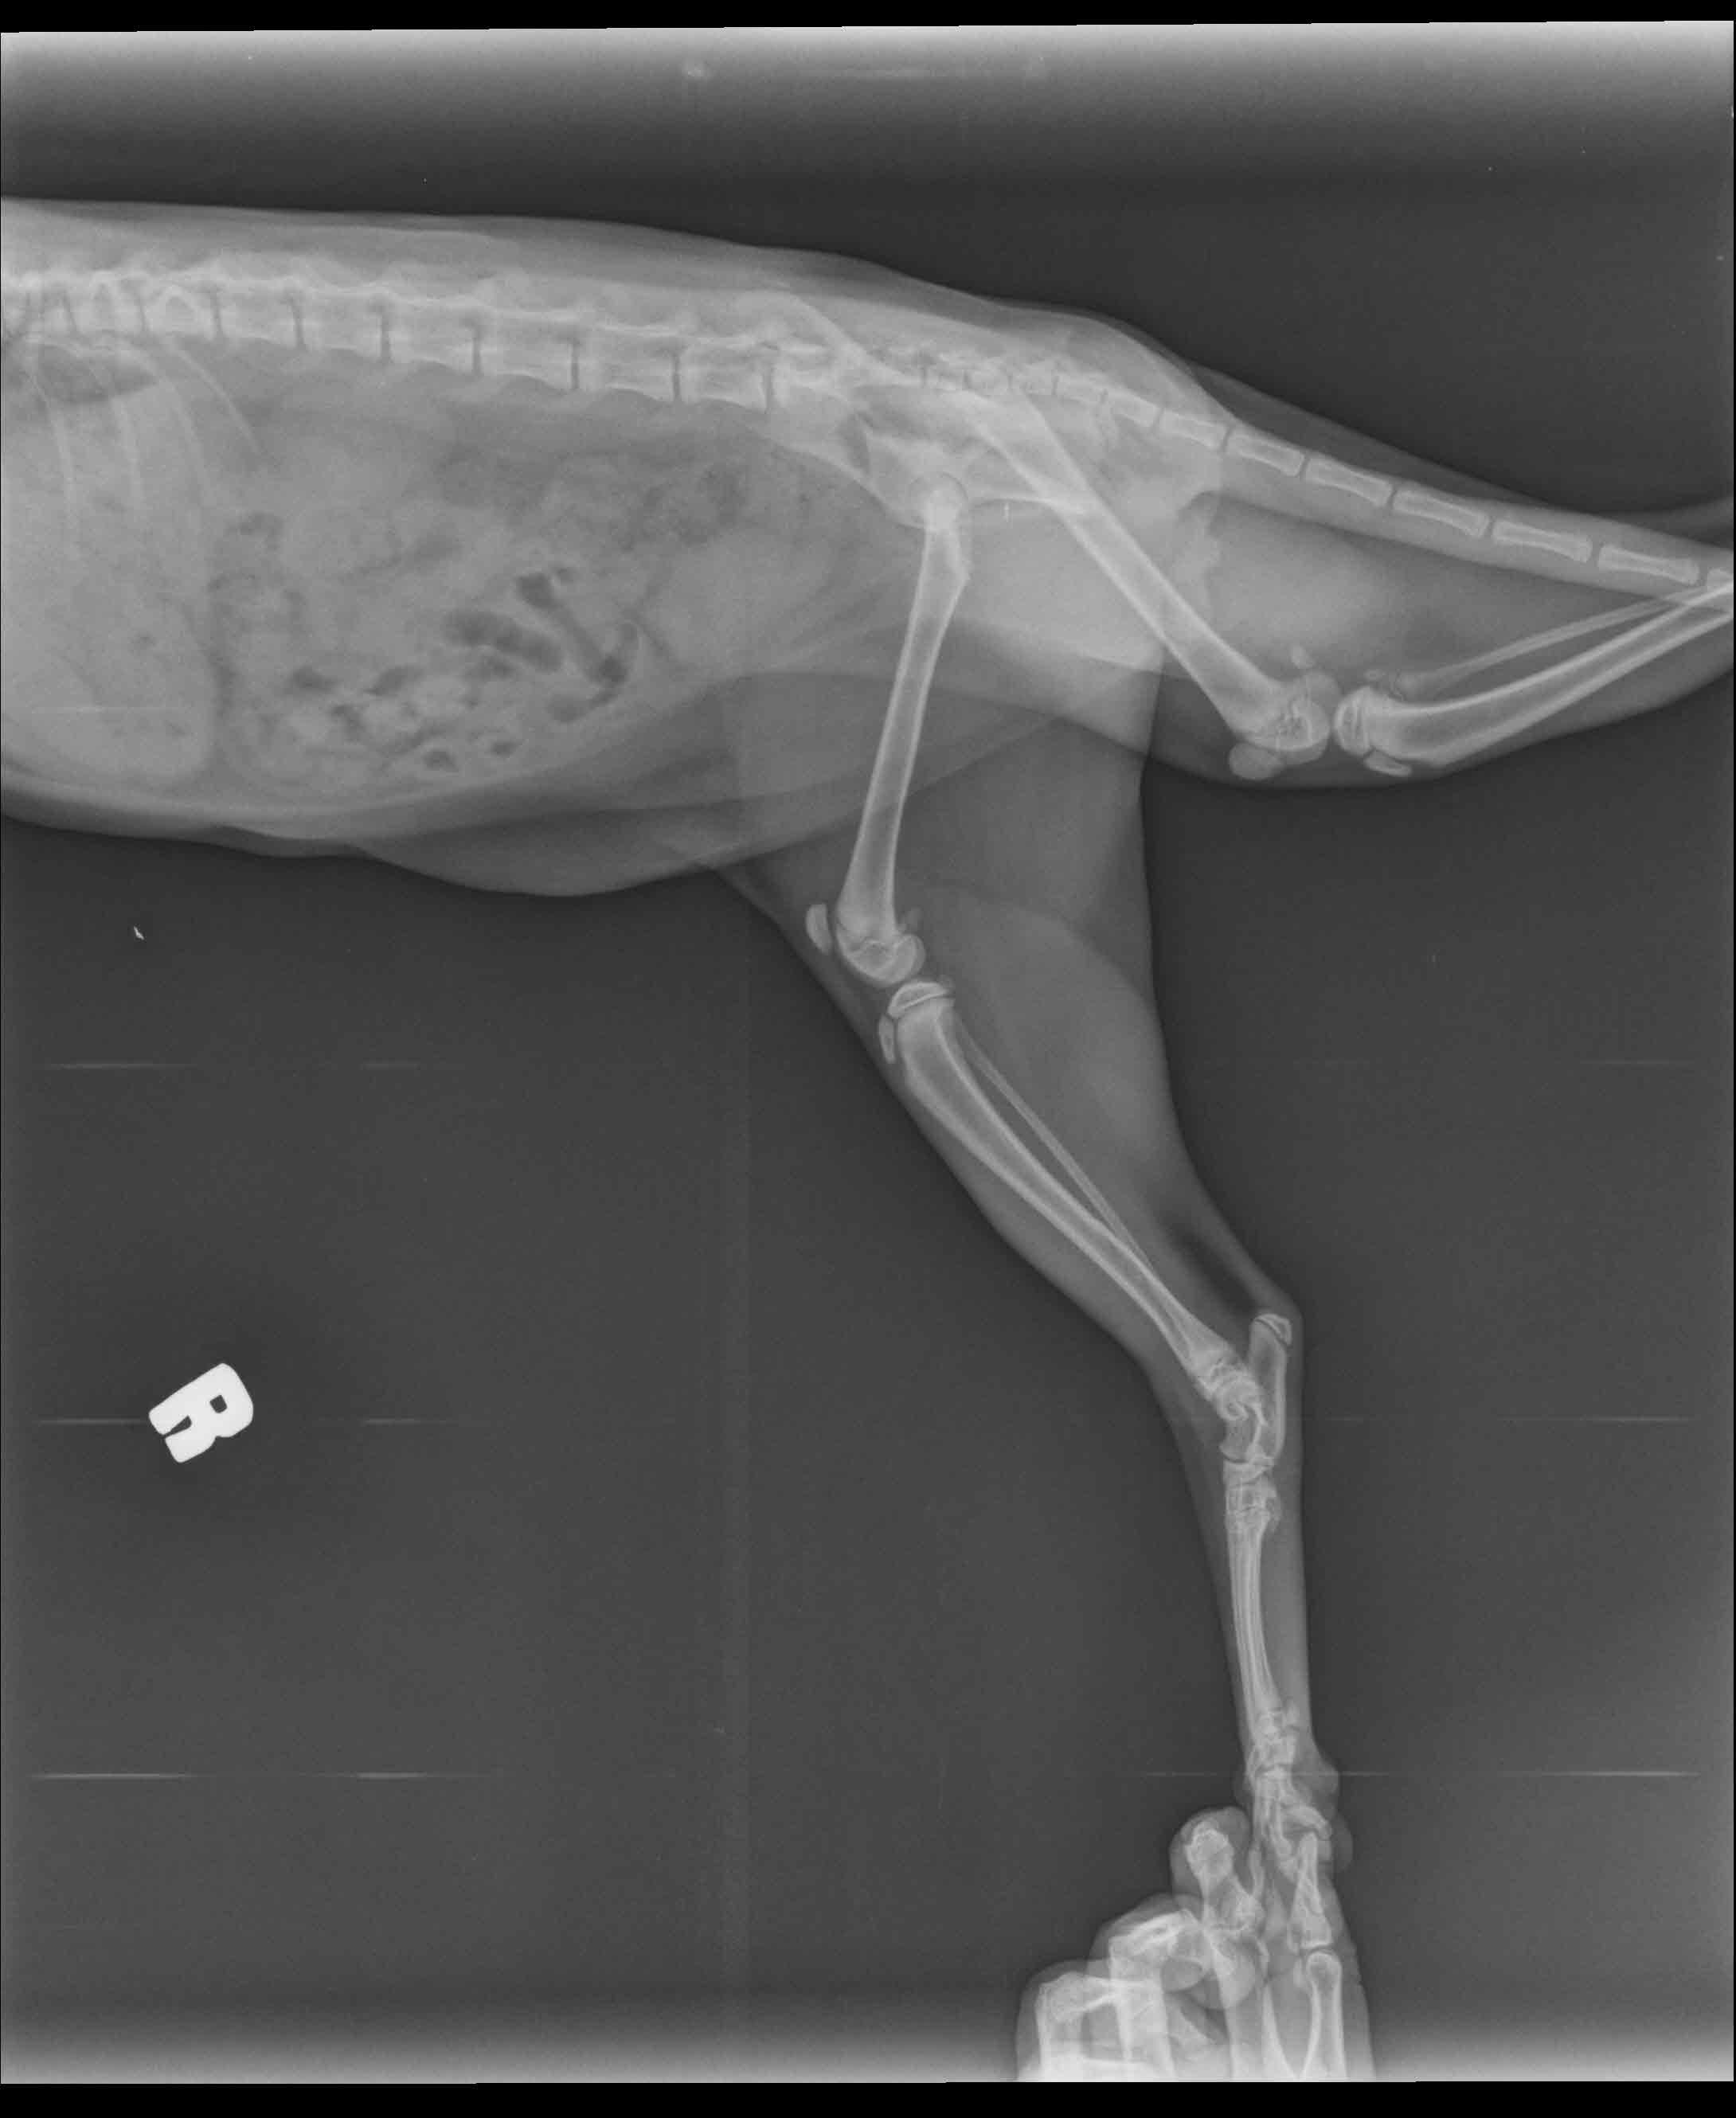

Hello, I have a five months male cat. While he was playing on the table, accidently he fallen down and screamed. After he stand up he start to not stepping on the foot. After veterinary control, they said his foot bone was broken. But i am not sure that it is true. In our country the veterinaries can lied about the situation for earning much money. I atteached the x-ray. Could you check is there a fracture?

I am pretty sure I can see a fracture of the tibia. If you look closely at the third picture and compare the two legs, the long bone right above the foot does not look the same as the other leg. These fractures can usually be healed with splinting or surgery, cage confinement, and pain management.

I am very sorry to hear about your kitty. Unfortunately it does appear he has a broken bone, though in the photo the bone I see broken is actually his leg bone- not the foot. If you look at the bones just above the foot/ankle, the larger of the two long bones has a fracture (this is the tibia). We would need to see an additional view of the bone to know how displaced the fracture is and the best course of action to repair the break.